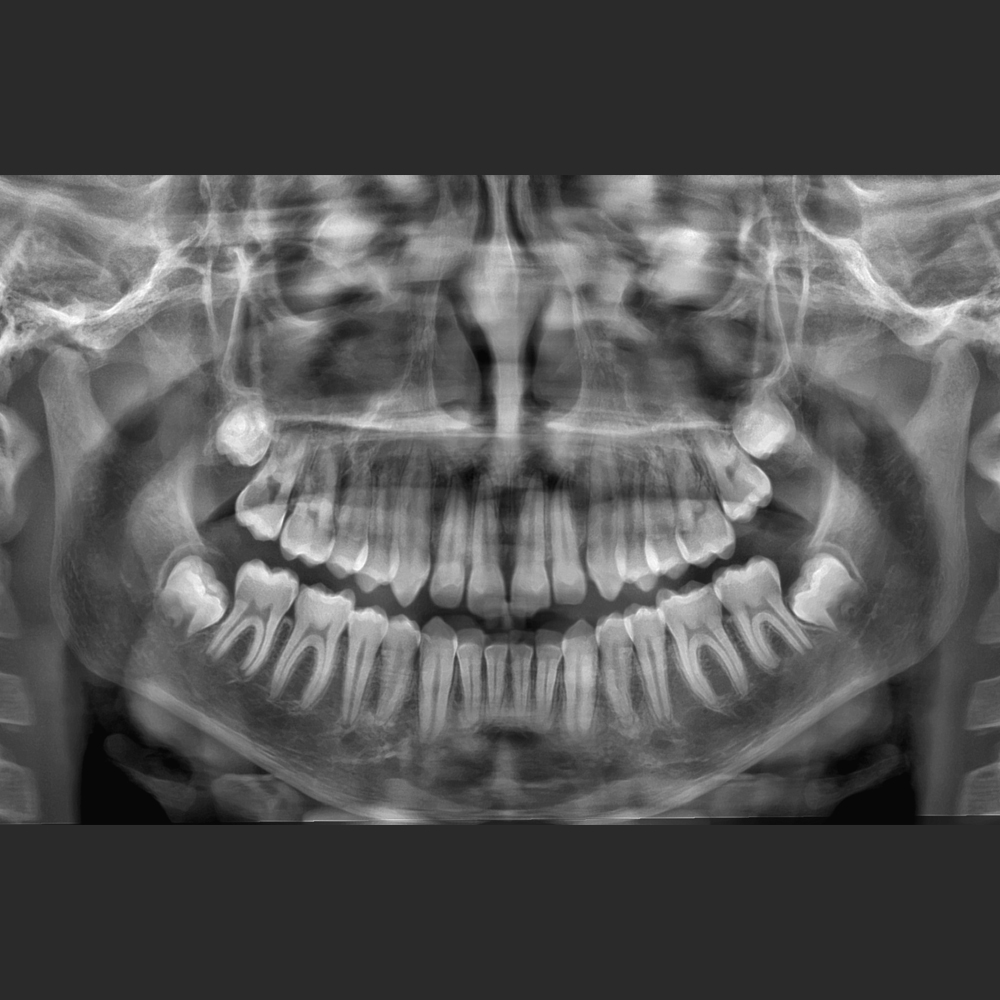

El Eagle 2D Pan/Ceph ofrece todos los exámenes en el perfil panorámico

(panorámica estándar, senos maxilares, baja dosis, bitewing, ATM, ortogonalidad perfeccionada, panorámica infantil y bitewing ortogonalidad perfeccionada)